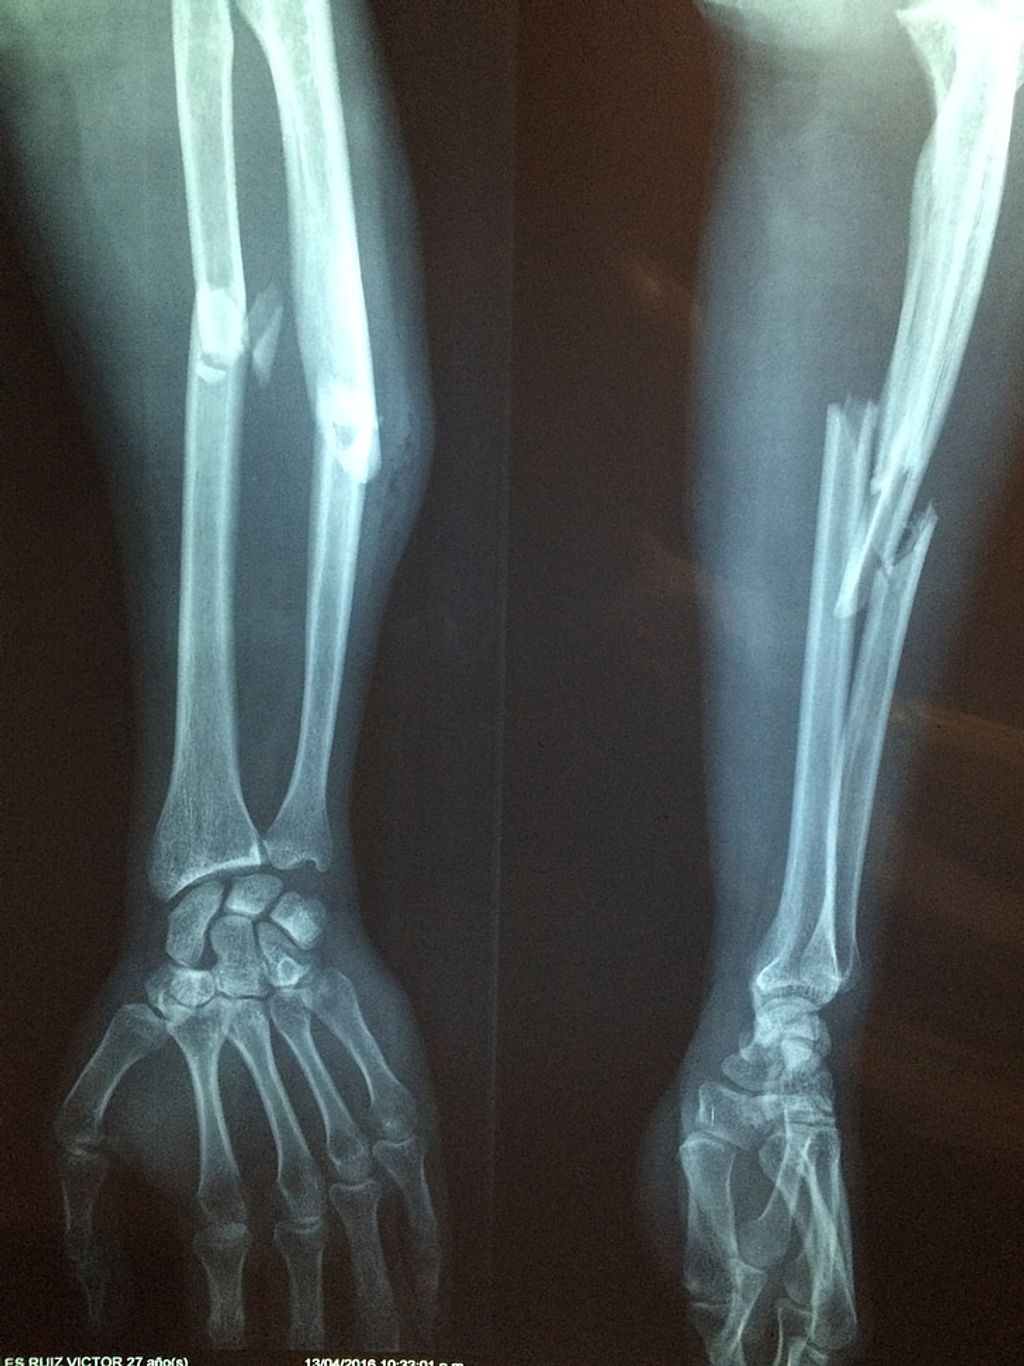

Injury Trauma or damage to the knee, such as ligament sprains, fractures, or meniscus tears

The most common imaging modalities we utilize include X-rays, magnetic resonance imaging (MRI), and ultrasound. X-rays are excellent for visualizing bone structures and can help us identify fractures or signs of osteoarthritis. MRI scans offer a more detailed view, particularly of soft tissues such as ligaments, tendons, and cartilage. Ultrasound is a real-time imaging technique that can assess the dynamic movement of the knee joint.

• X-rays: Recommended for suspected fractures, osteoarthritis, or bone tumors.

• MRI: Indicated for soft tissue injuries, ligament tears, or meniscal damage.